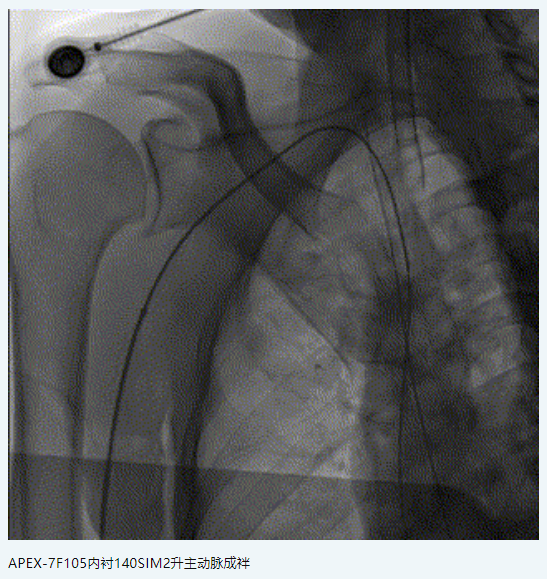

橈動脈系統(tǒng):APEX TRA SYSTEM 7F-105cm+140cm-SIM2

中間導管:中天中間導管 5F-125cm

微導絲:瑞康通0.014”神經(jīng)導絲

球囊:Neuro LPS顱內(nèi)球囊擴張導管2.0*15mm

支架:NOVA顱內(nèi)藥物洗脫支架2.25*15mm

6.7F APEX TRA SYSTEM橈系統(tǒng):1、外徑細(2.32mm),對橈動脈侵擾小,內(nèi)腔大(0.081”):可兼容5F中間導管高到位;經(jīng)橈專用,弓部支撐性較長鞘、導引導管、中間導管、DA更強;APEX橈系統(tǒng)配套有130/140cm長SIM2,長SIM2管同軸治療可避免交換失敗,使顱內(nèi)病變更加便捷。